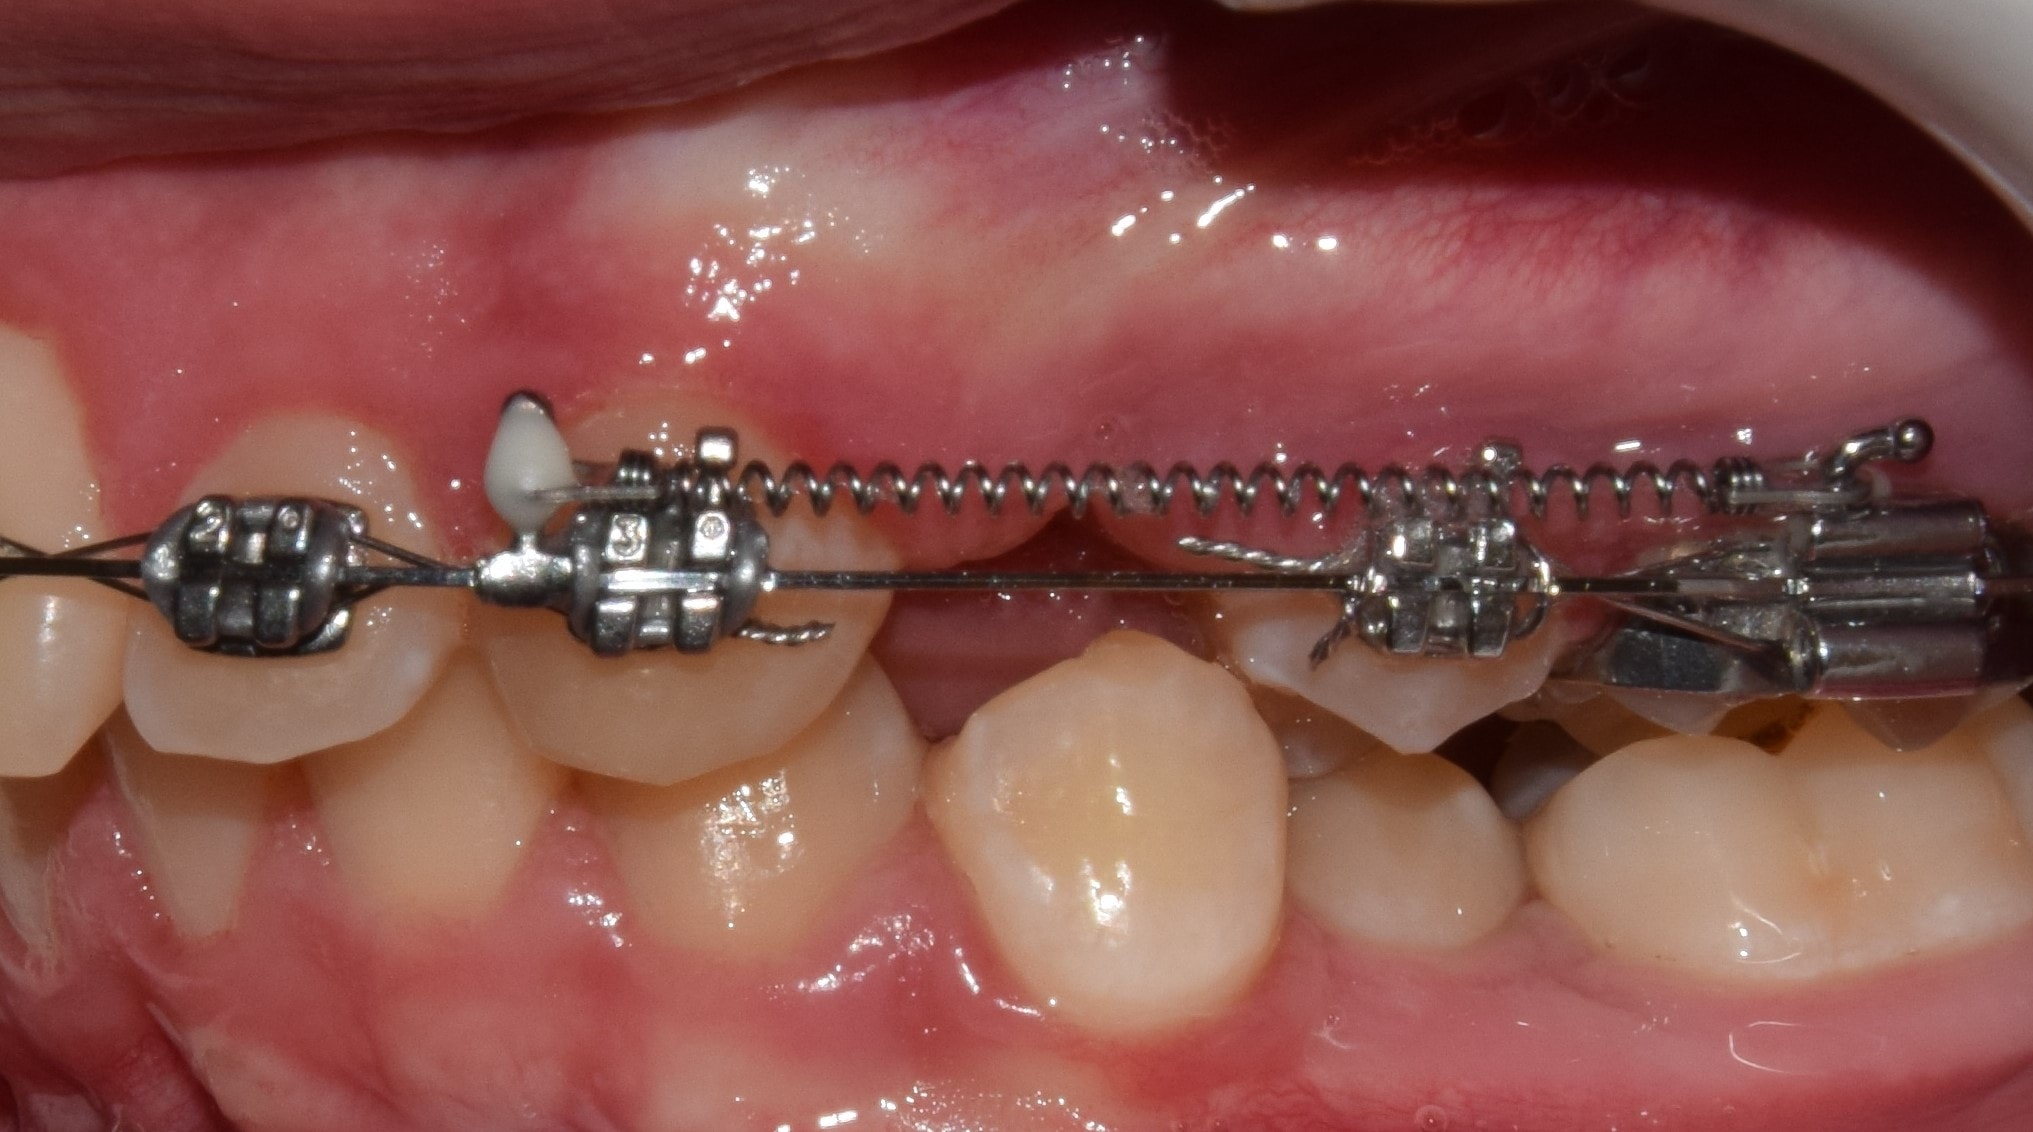

D-gainer

A D-gainer készülék tulajdonképpen egy részleges rögzített fogszabályzóként fogható fel, melyet elsősorban gyerekeknél, korai vagy késői vegyesfogazatban alkalmazunk. Szintén önligírozó bracketeket használok a D-gaineres kezeléseknél. A rendszert a felső első nagyőrlők, és a négy felső metszőfog alkotja, melyeket ugyanúgy fogszabályzó ívvel kötünk össze., mint a teljes rögzített fogszabályzónál. A nagyőrlők és a metszőfogak közé az ívre egy hosszú tolórugót helyezek. A D-gainerrel jelentős mértékű helyet lehet teremteni a felső fogívben, illetve nagyfokú oldalirányú tágítás végezhető. Alkalmas az előrehelyezett felső nagyőrlők hátravitelére, főként hátraforgatására. Tipikus indikációja, ha a felső állcsontban nincs elegendő hely a szemfogaknak.